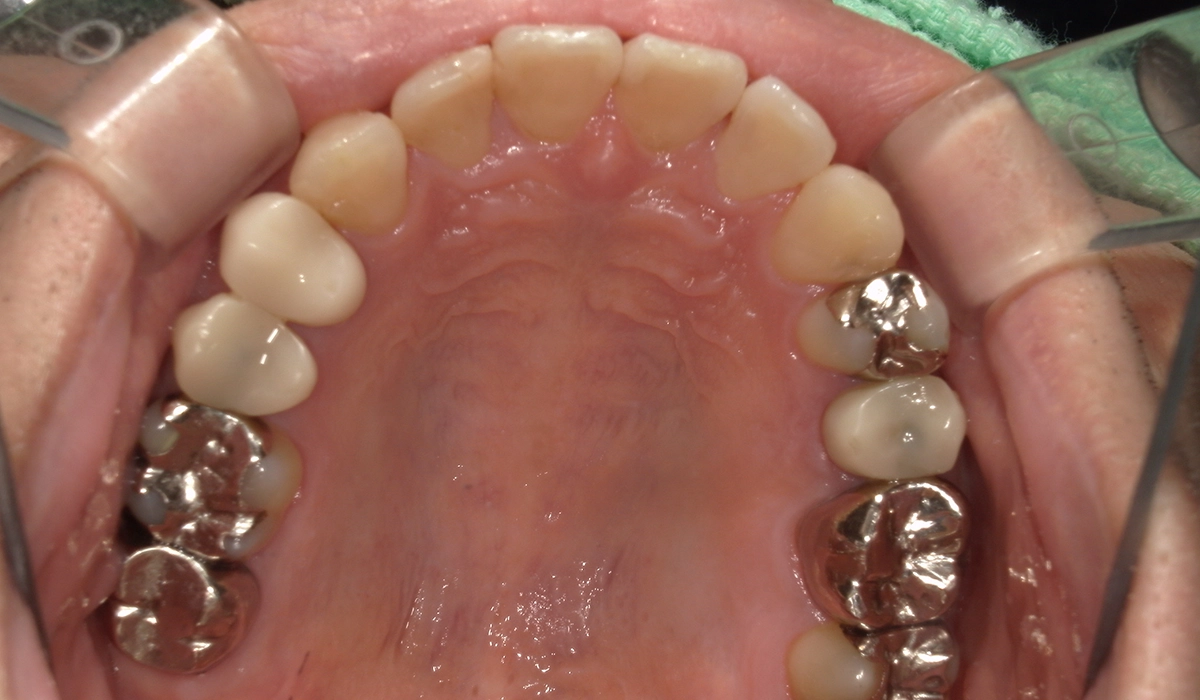

術前:上顎

術後:上顎